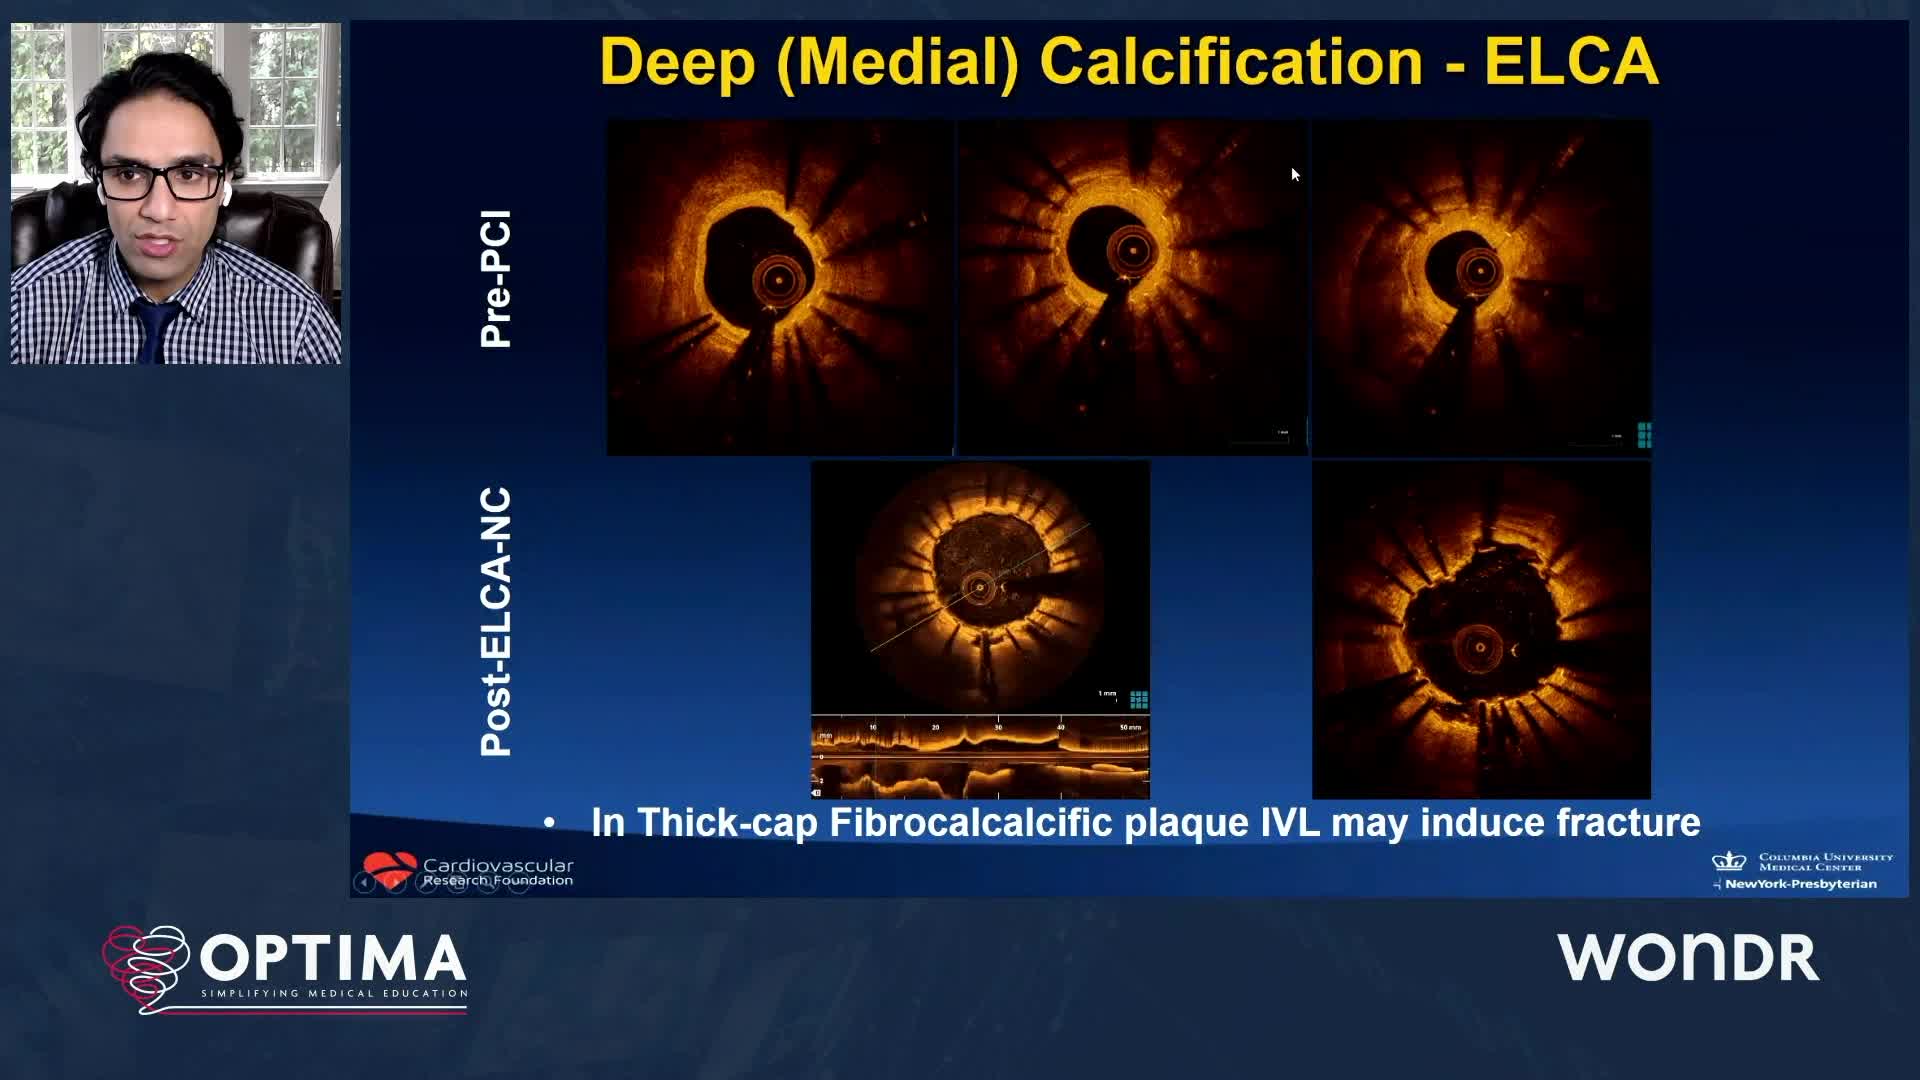

Treatment of coronary arterial calcium (CAC) has being redefined. We explore the interaction between CAC and patient...